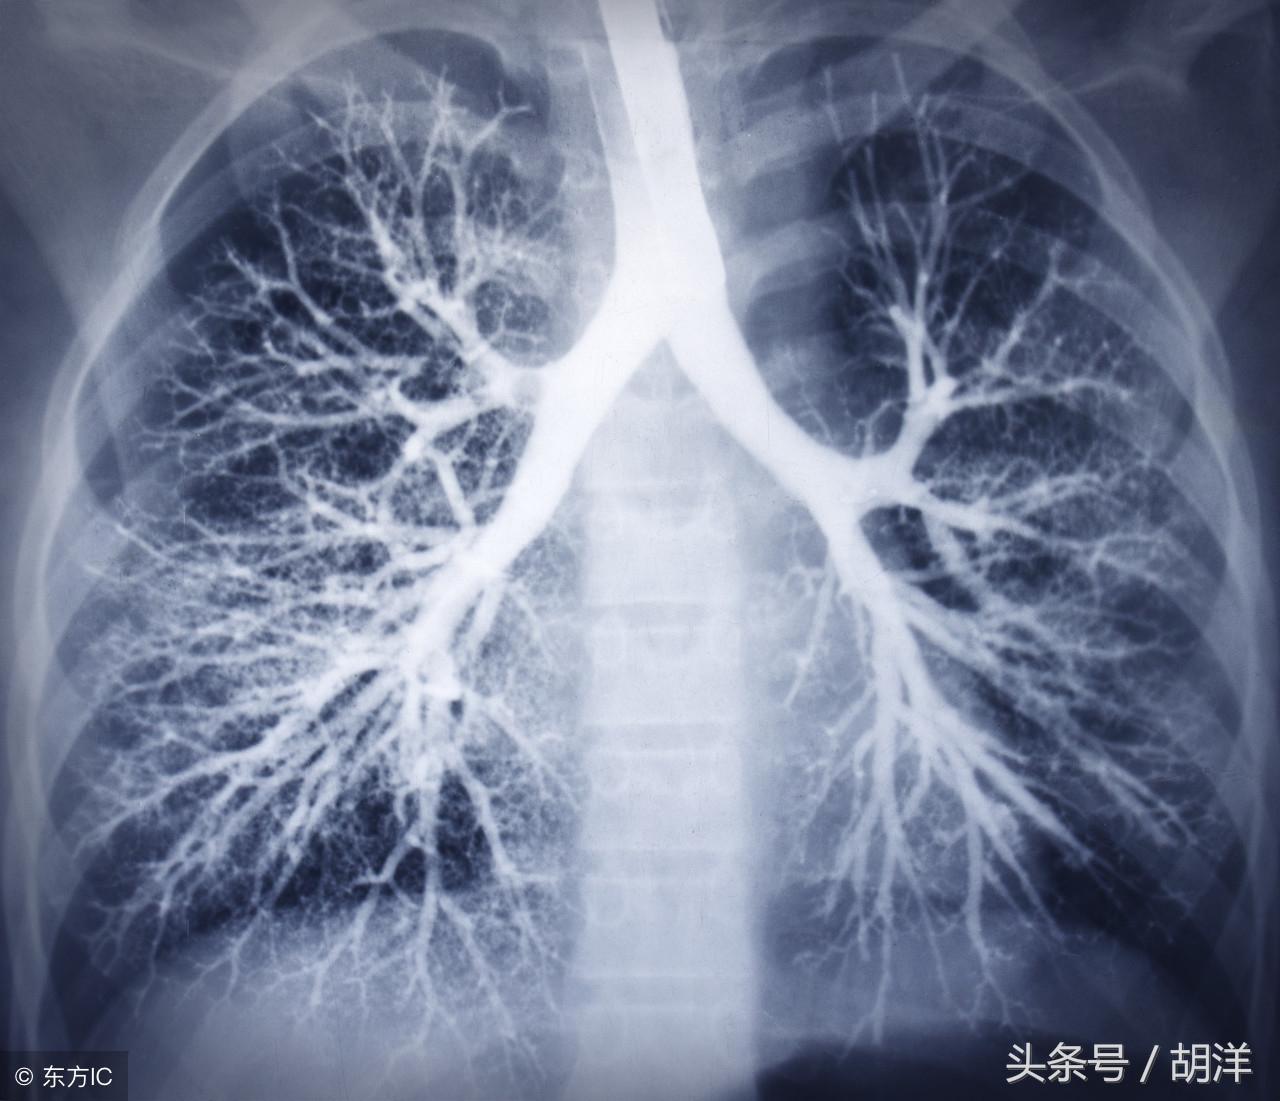

咳血又称咯血,是呼吸科一个比较严重的症状,由于其可能提示肺部肿瘤等严重疾病而受到重视,但事实上在引起咯血的病因中,肺部恶性肿瘤所占的比例并不是很大,但很多人因咯血而焦虑异常,特别是咯血久治不愈情况下,更加令人无法正常的生活和学习,那么哪些疾病可能导致反复发作痰中带血或者咳出满口鲜血呢?

支气管扩张是一种支气管管壁结构破坏性疾病,正常情况下,支气管是一个带有弹性,拥有一定管径的能够维持正常呼吸通气的结构,当管壁结构受到破坏时,气管会受到被动的牵拉而扩张,管壁的血管由于弹性较小,容易被撕扯呈血管瘤改变,一旦胸腔内血流压力增大可能冲破血管瘤变薄的管壁而导致大咯血,少量渗血时则呈现为痰中带血。